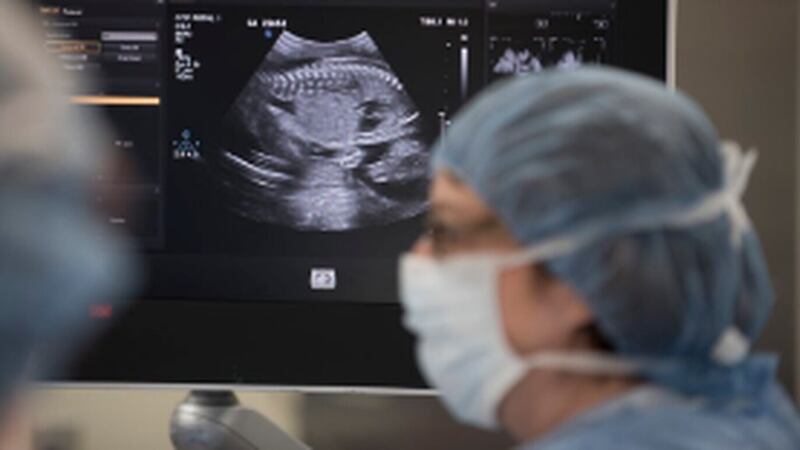

Surgeons then used an ultrasound to find the placenta and fetus. A tiny incision is made so doctors can see the back of the fetus and repair the spina bifida lesion.